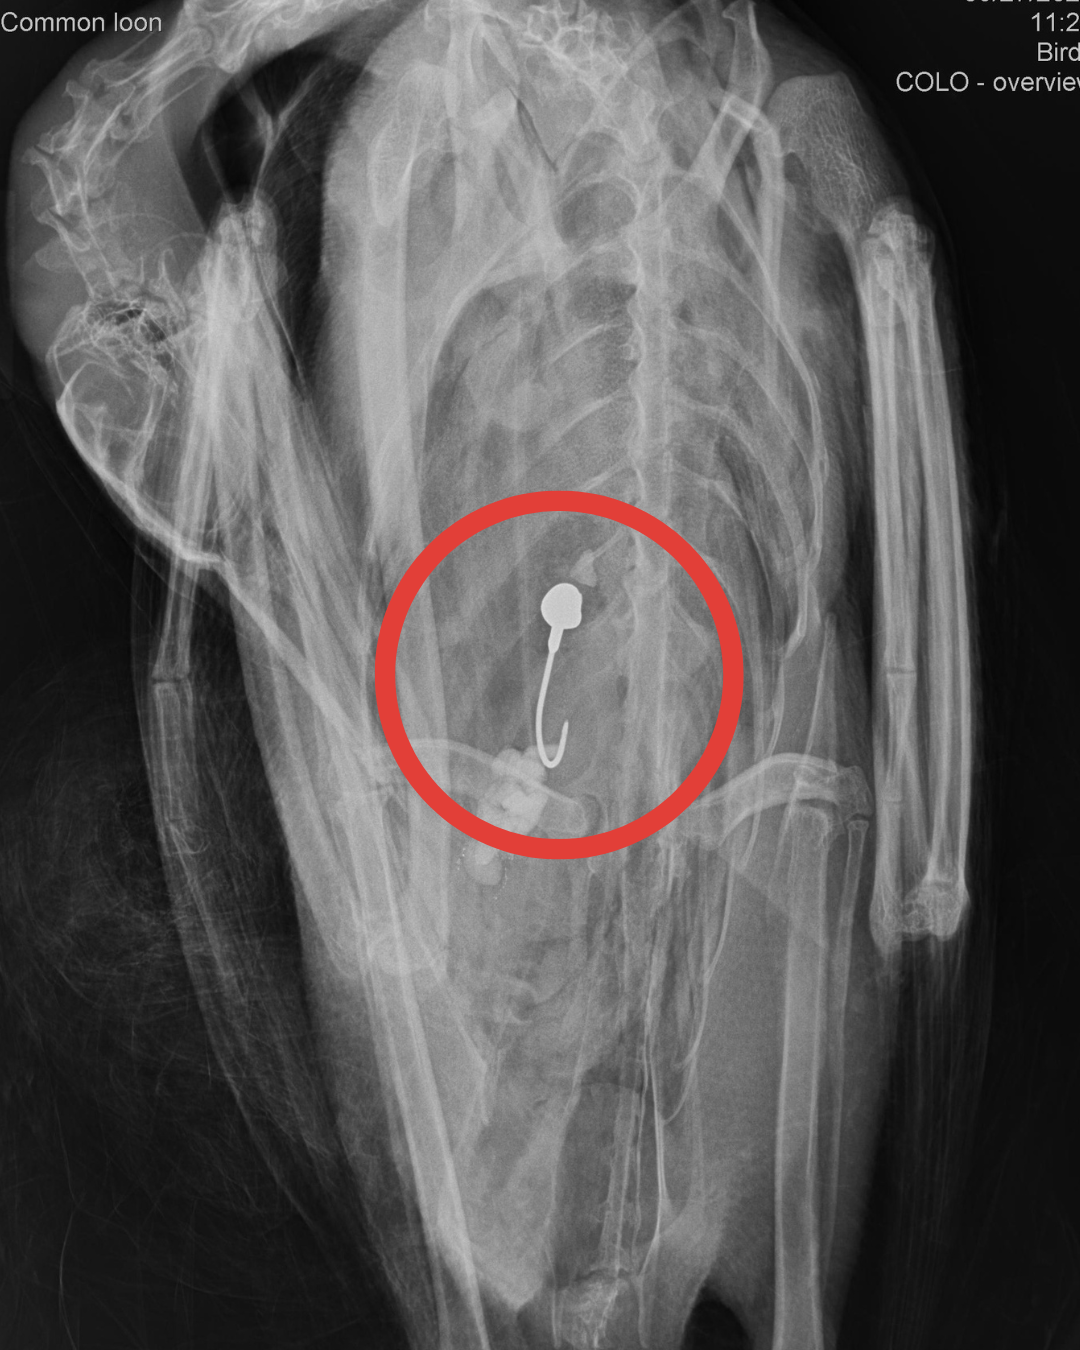

Lead from lead fishing tackle poses a significant risk to birds that prey on fish, and lead ammunition to birds that scavenge deceased animals.

The number one way that loons ingest lead jigs and sinkers is when they eat a fish that has broken a line and has lead tackle in its mouth or stomach.

Sometimes loons swallow lead sinkers when they purposely swallow pebbles and small stones to help aid in digestion. A lost or discarded sinker can easily be mistaken for another pebble.

Because of the size of fish that loons can swallow, they are capable to ingesting lead tackle up to 2.5 inches in size. Painted jigs are still dangerous to loons - the paint is easily broken down in the gizzard, exposing the lead weight.